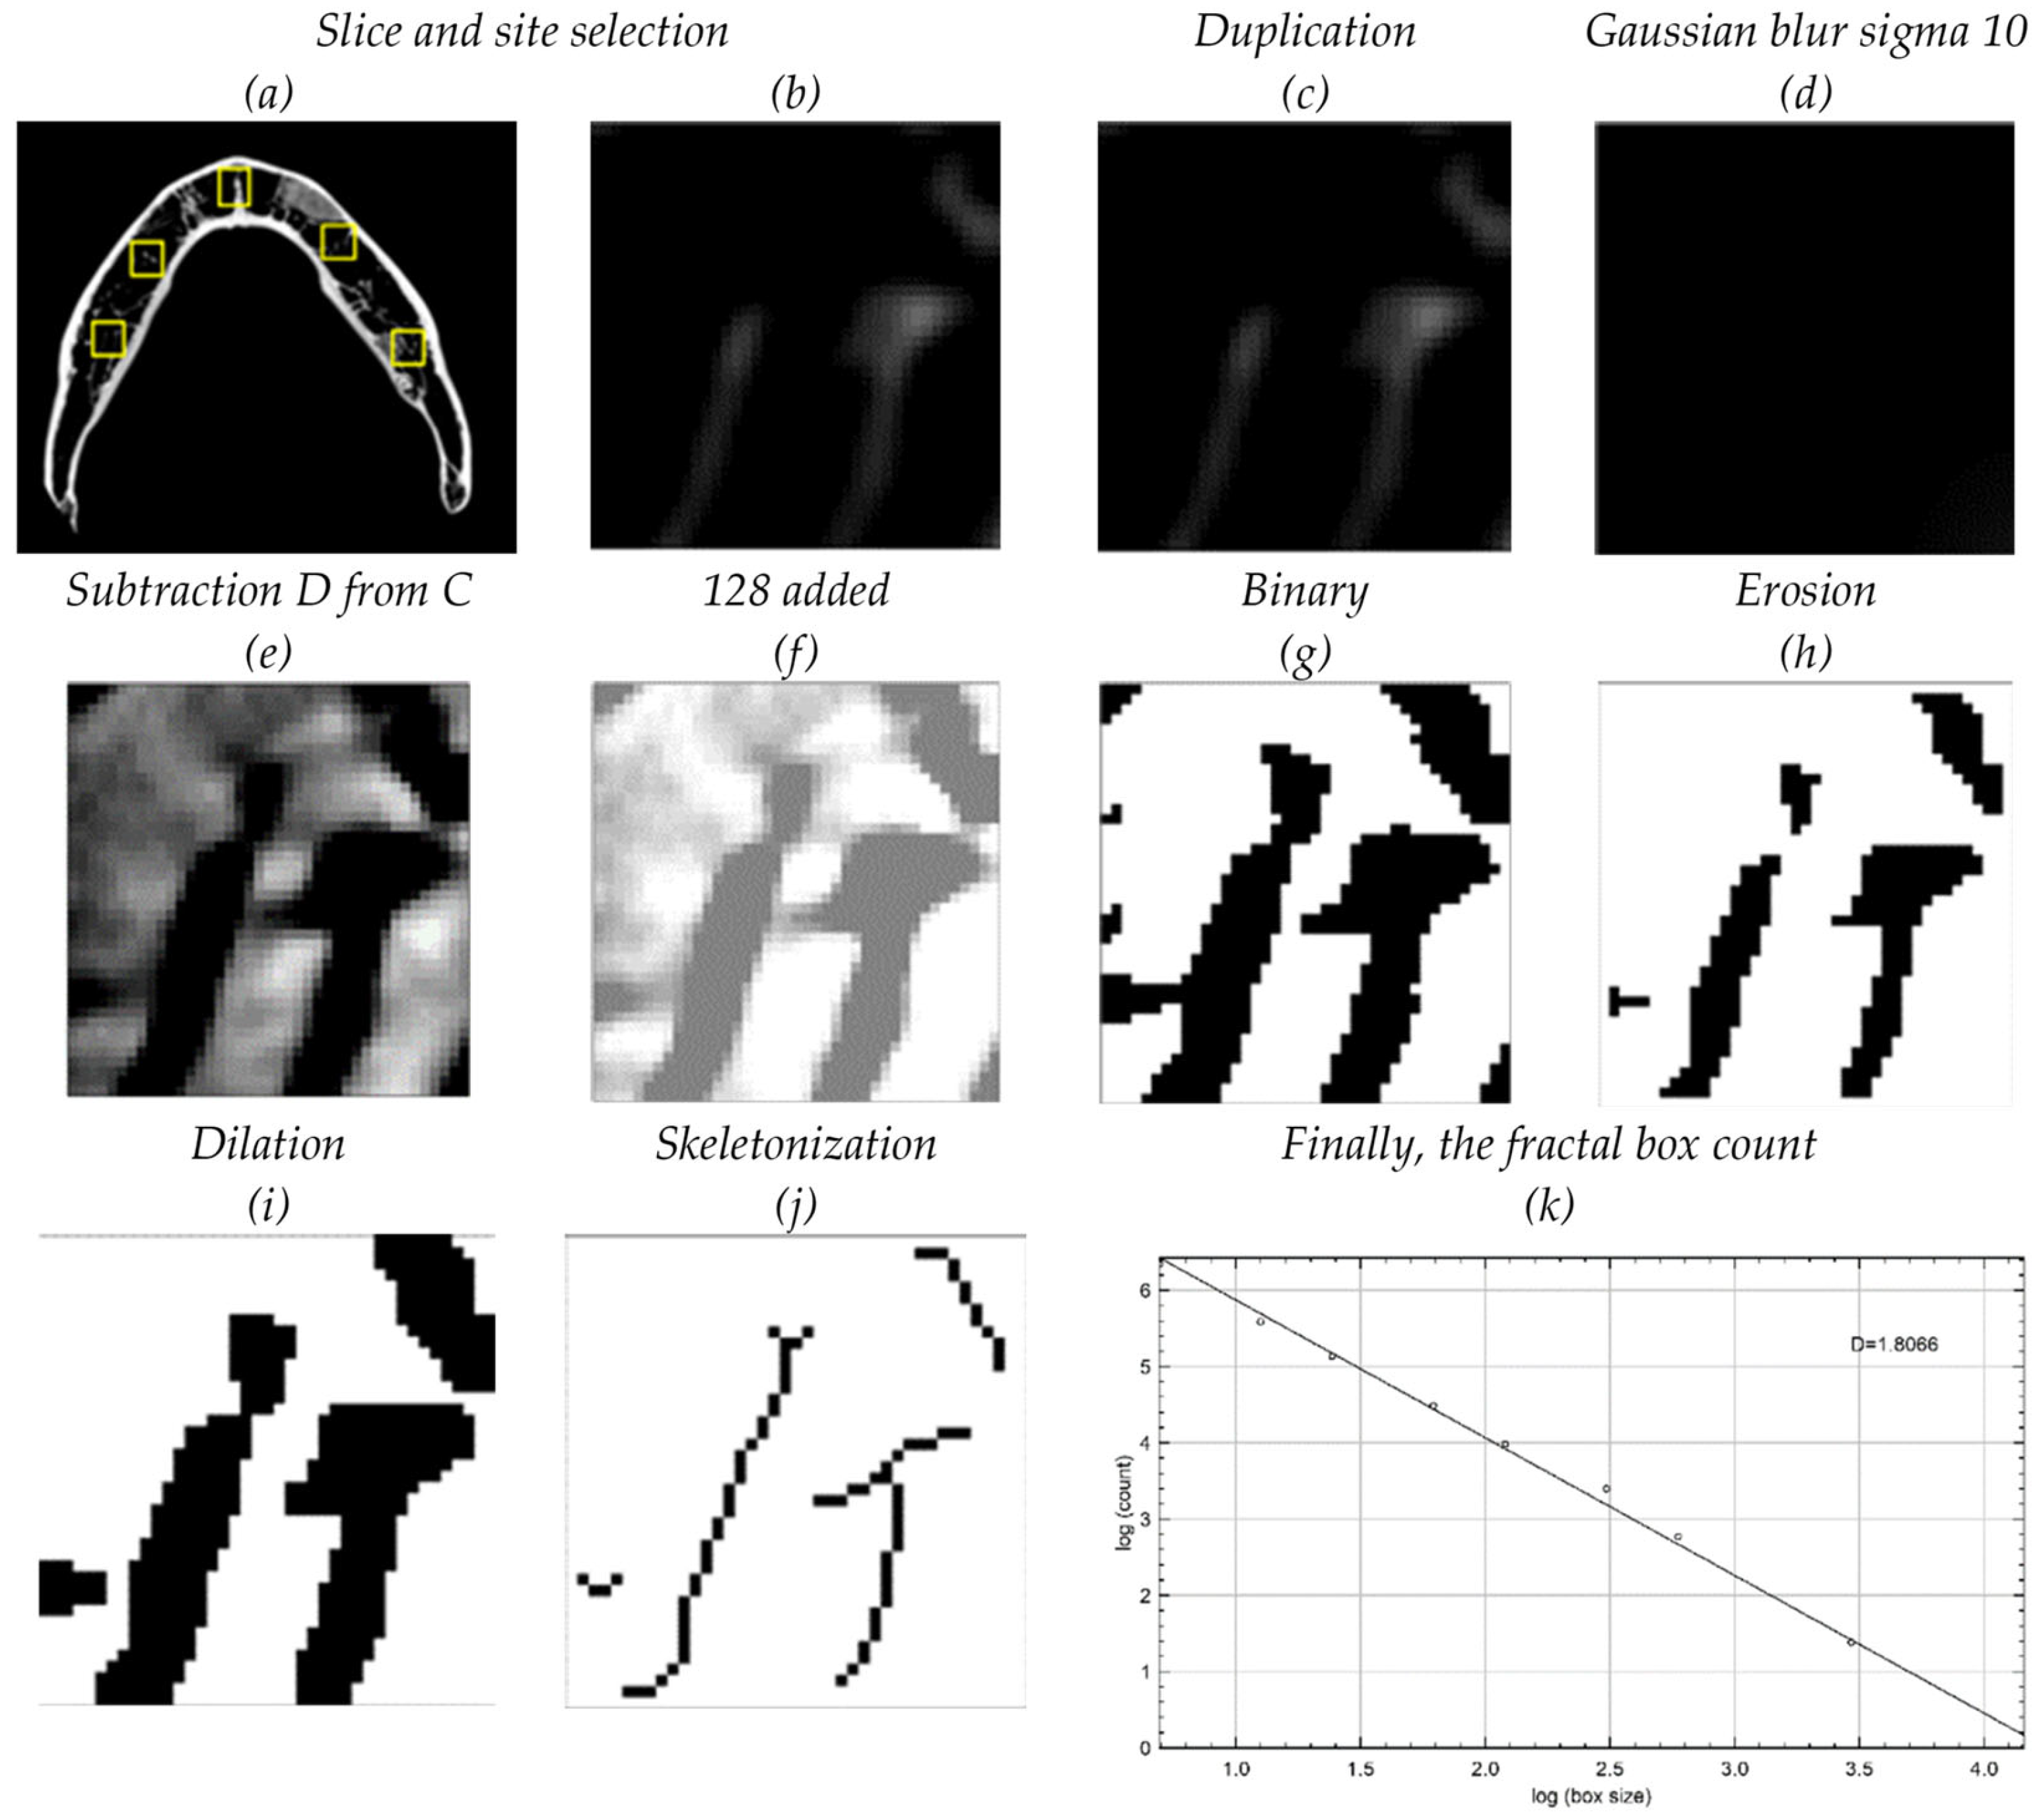

2. Materials and Methods